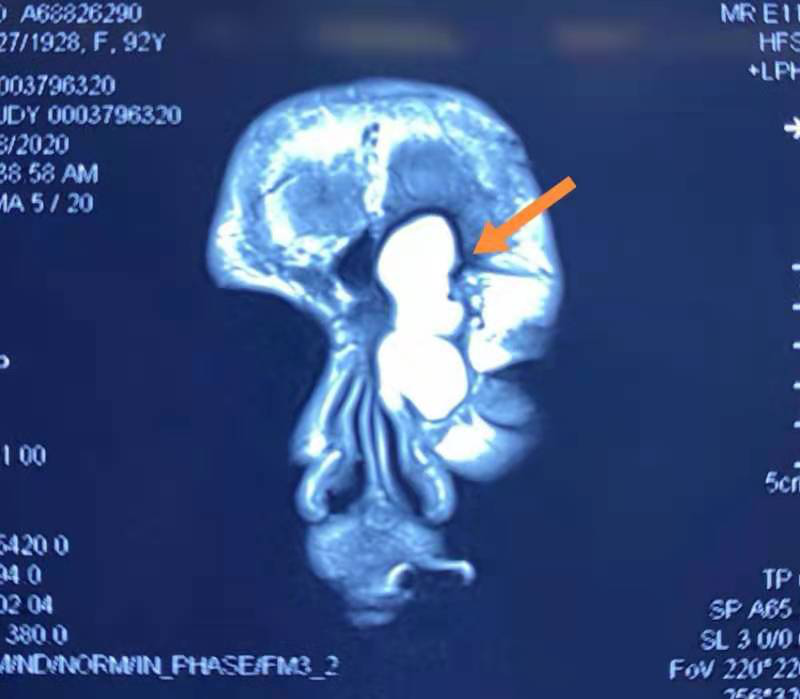

據(jù)介紹,一年前依姆及家人發(fā)現(xiàn)依姆的鼻根部及眉頭越來(lái)越腫大,并出現(xiàn)了眼睛脹、頭痛等不適。到醫(yī)院檢查后,醫(yī)生告知是臨床上少見(jiàn)的鼻竇巨大囊腫,急需手術(shù)治療。但考慮到依姆高齡且患有罕見(jiàn)的“室間隔基底顯著增厚伴左室流出道梗阻(重度)”手術(shù)風(fēng)險(xiǎn)極高,多家醫(yī)院皆不敢接診。近期,依姆慕名來(lái)到福建省人民醫(yī)院耳鼻喉科就診。陳曦主任醫(yī)師接診病人后評(píng)估手術(shù)指征明確,并第一時(shí)間與麻醉科溫莉副主任醫(yī)師一同評(píng)估患者情況,為手術(shù)的實(shí)施保駕護(hù)航。經(jīng)過(guò)精心的術(shù)前準(zhǔn)備,10月28日,陳曦主任為患者實(shí)施了“鼻腔微創(chuàng)射頻消融術(shù)”,手術(shù)過(guò)程非常順利。術(shù)后依姆沒(méi)有任何并發(fā)癥,康復(fù)出院。做到了微創(chuàng)與快速康復(fù)的相結(jié)合。

鼻竇囊腫多發(fā)于篩竇,是一種良性腫物,但當(dāng)囊腫增大時(shí)可累及周圍結(jié)構(gòu),包括眼眶和顱底。囊腫繼發(fā)感染發(fā)展成膿囊腫破壞性變大,篩竇囊腫的患者常常是出現(xiàn)眼部癥狀才來(lái)就醫(yī)。

手術(shù)是鼻竇囊腫唯一的治療方法。目前首選鼻內(nèi)鏡鼻內(nèi)進(jìn)路手術(shù)輔助等離子具有創(chuàng)面小、出血少等特點(diǎn)。